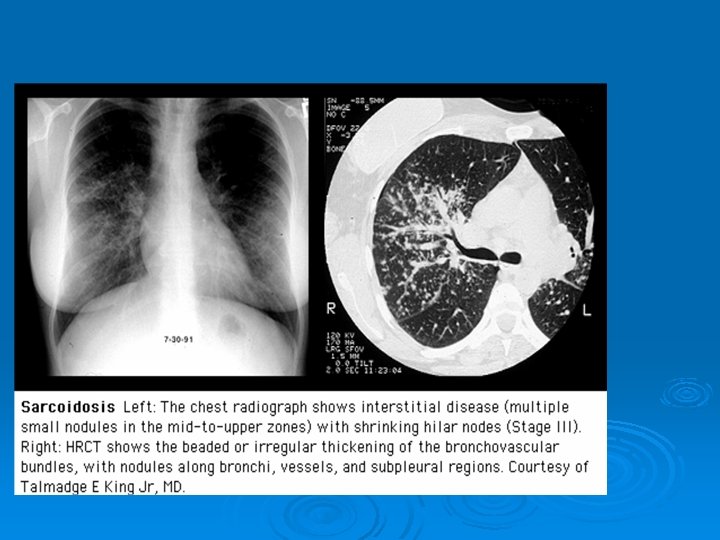

PA AKCİĞER GRAFİSİ Ø Grafiye göre evreleme yapılır: Evre 0: normal Ø Evre 1: bilateral hiler, mediastinal veya paratrakeal LAP Ø Evre 2: evre 1 + parankimal infiltrasyonlar Ø Evre 3: LAP ın eşlik etmediği diffuz pulmoner parankimal infiltrasyonlar Ø Evre 4: LAP ın eşlik etmediği fibro-kistik interstisyel akciğer hastalığı Ø

HRCT Ø Akciğer grafisine göre daha duyarlı Ø Paratrakeal, pretrakeal, paraaortik ve subkarinal adenopatilerde tespit edilebilir